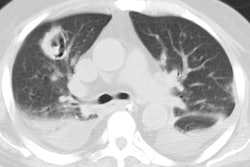

CXR demonstrates migratory infiltrates, but after 1 to 2 months the lesions become stable nodules or cysts predominantly in the lower lobes. Pleural effusions can be seen.CT findings include poorly marginated peripheral or subpleural nodules measuring approximately 2cm (up to 74% of cases) with surrounding ground-glass and a streaky opacity connecting the nodule to the pleural surface [3], pleural effusion, hydropneumothorax, airspace consolidation, and thin walled cysts [1,2].